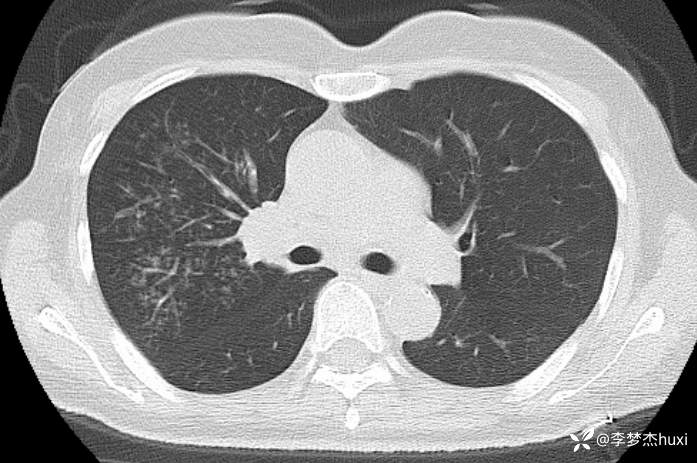

女性53岁,腮腺癌术后反复咳嗽、咳痰,胸部CT以树芽征为特点改变,最可能的是哪种疾病

【现病史及既往史】: 1.患者中年 女,患者于入院前5天无明显诱因出现咳嗽,咳痰,为黄绿色痰,量少,不易咳出,伴发热,最高体温不详,伴周身乏力,无胸痛,无呼吸困难,无恶心、呕吐,无腹痛、腹泻,无抽搐及意识障碍,院外未诊治,症状无好转,今患者及家属为进一步诊治前来我院就诊,门诊查胸部CT:右肺上叶占位性病变应考虑,右肺上叶空洞;右肺下叶占位?双肺炎症,支气管炎?右肺门淋巴结增大,双肺实性结节,纵隔结节,主动脉及冠状动脉钙化,右侧乳腺结节?建议结合超声,建议结合临床复查。门诊以“肺炎”收入院 。

2.既往高血压病史20余年,最高达180/?mmHg,目前口服“缬沙坦胶囊、硝苯地平控释片、酒石酸美托洛尔”等药物治疗,血压未监测;2008年因右侧腮腺腺样囊性癌于天津肿瘤医院行手术治疗,术后给予放化疗,2019年肿瘤原位复发,于北京大学口腔医院再次行手术治疗,2023-8发现肿瘤侵犯右耳道,目前口服仑伐替尼治疗约12个月;2023-11开始应用帕博利珠单抗注射液免疫治疗,患者右肺上叶占位,2024-7于沧州市中心医院行穿刺活检,病理:腺样囊性癌,2024-08于北京市某医院行“肺部射频消融术”;患者术后时常呛咳,否认“冠心病、糖尿病”病史,否认“肝炎”、“结核”等传染病史;否认外伤史,无输血史;否认食物、药物过敏史,预防接种史不详,系统回顾无特殊。。

【临床诊断】: 1.肺炎

2.肺恶性肿瘤 (腺样囊性癌)射频消融术后。